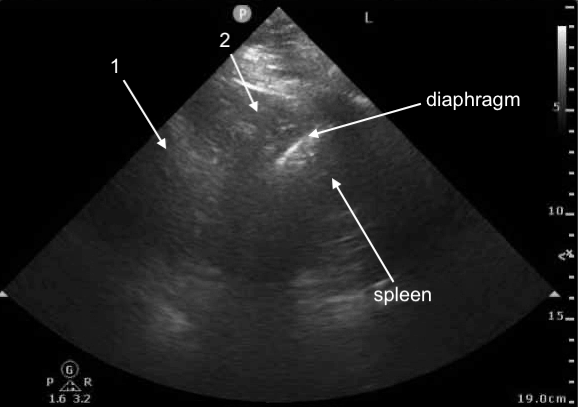

POCUS Image 1 - left mid-posterior axillary line, probe marker cephalad, attempt to visualize left hemidiaphragm

(not the best windows, structures a bit challenging to see clearly, we shall try our best with these)

4/

What are structures labeled 1 and 2 (same structures in both images)?

Spleen and diaphragm are difficult to see in this still image, so those are labeled

10/